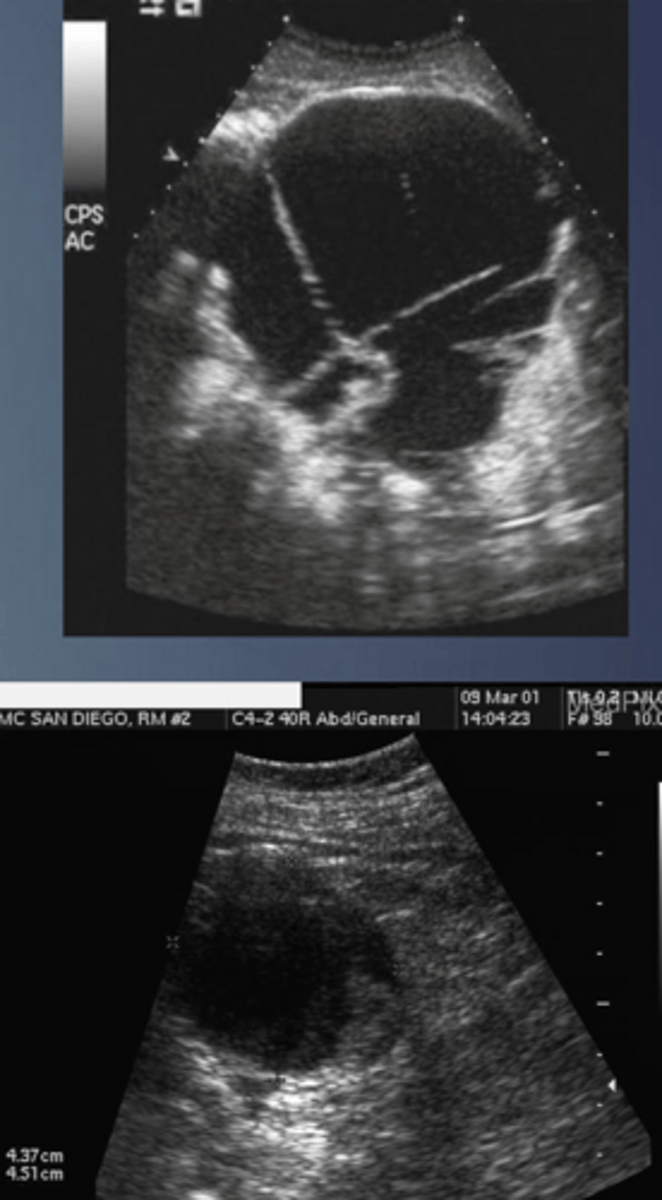

True Cyst Sonographic Appearance

-round to oval

-smooth

-thin, well defined walls

-anechoic

-w/ posterior enhancement

-may be multilocular

-be sure to differentiate from fluid (surrounding GI structures)

True Cyst